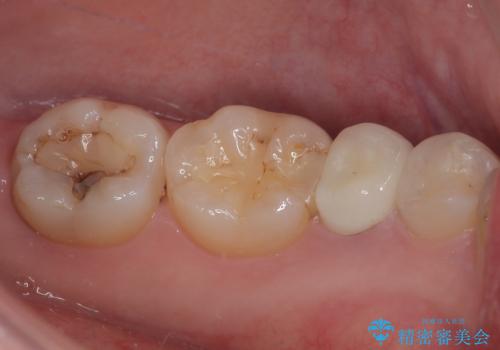

- 左下の被せものが割れたとのことで来院された患者様です。検査の結果、左下の前から4番目の歯はセラミックインレー修復、左下の5番目のところはオールセラミッククラウンによる補綴治療を行っていくことにしました。

拡大鏡視野下で被せもの、虫歯の除去を行い、オールセラミッククラウン、セラミックインレーに適した形に整えました。

適合の良い被せものが入り、審美面も気に入っていただけました。被せものが割れていたという経緯もあったため少しだけ被せものの厚みを多めに確保してあります。